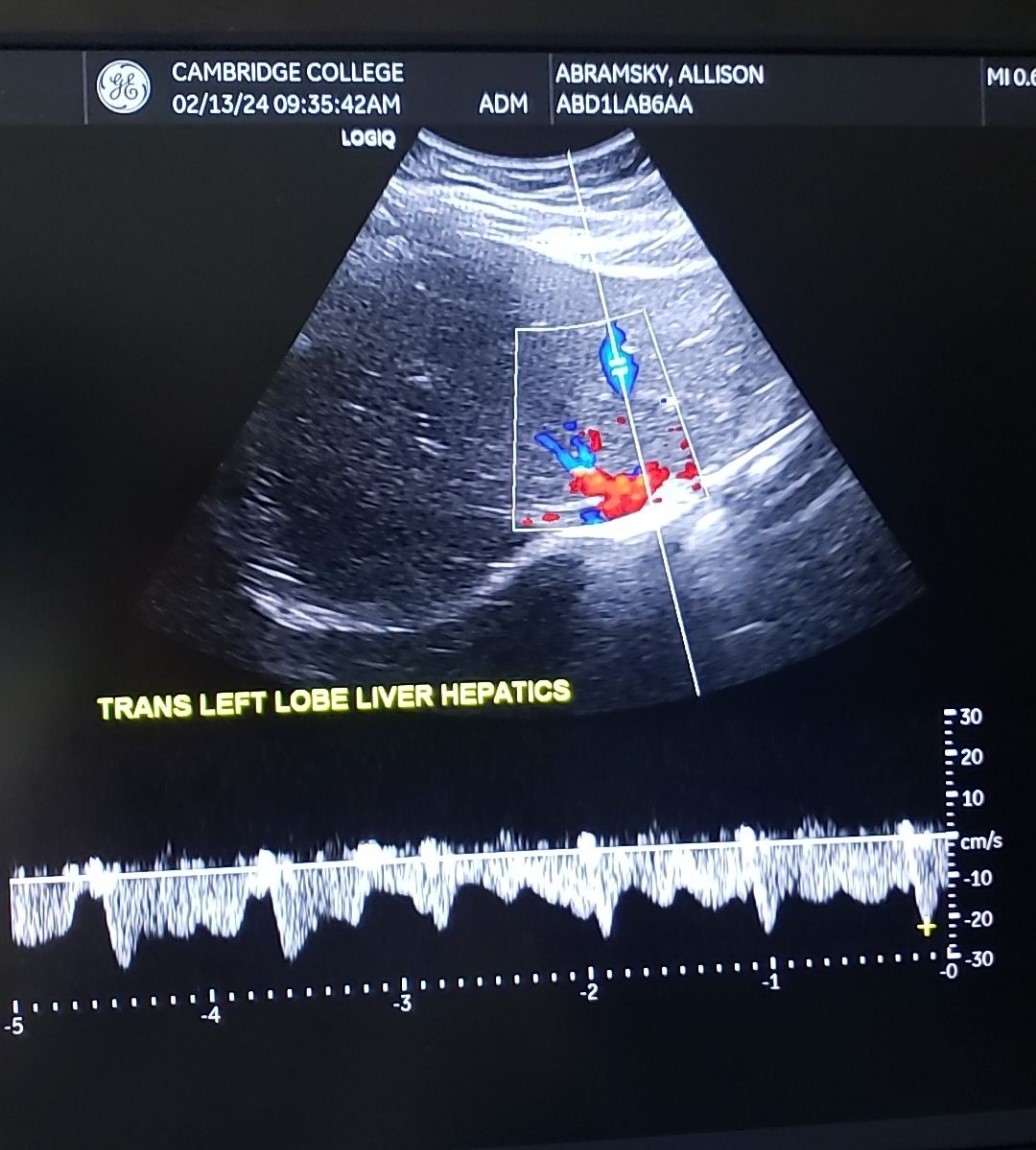

Trans LLL w/ Hepatics - color

19

New cards

Trans LLL w/ Hepatics - PW doppler